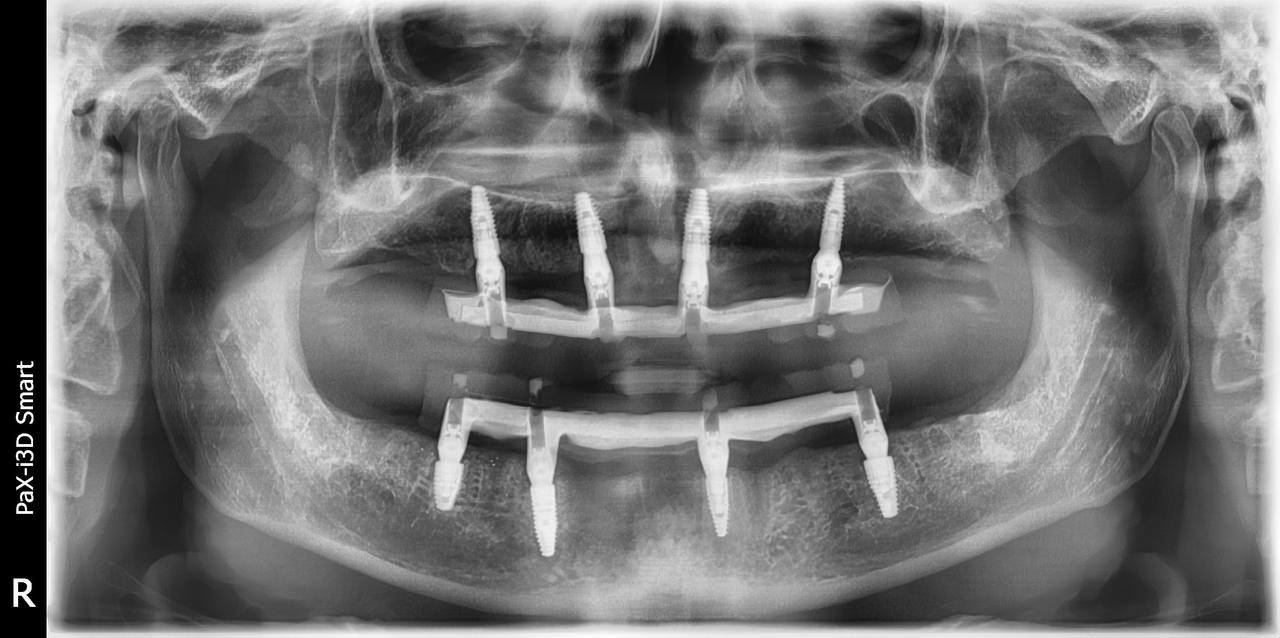

All on 4

Zdjęcia wykonanych zabiegów